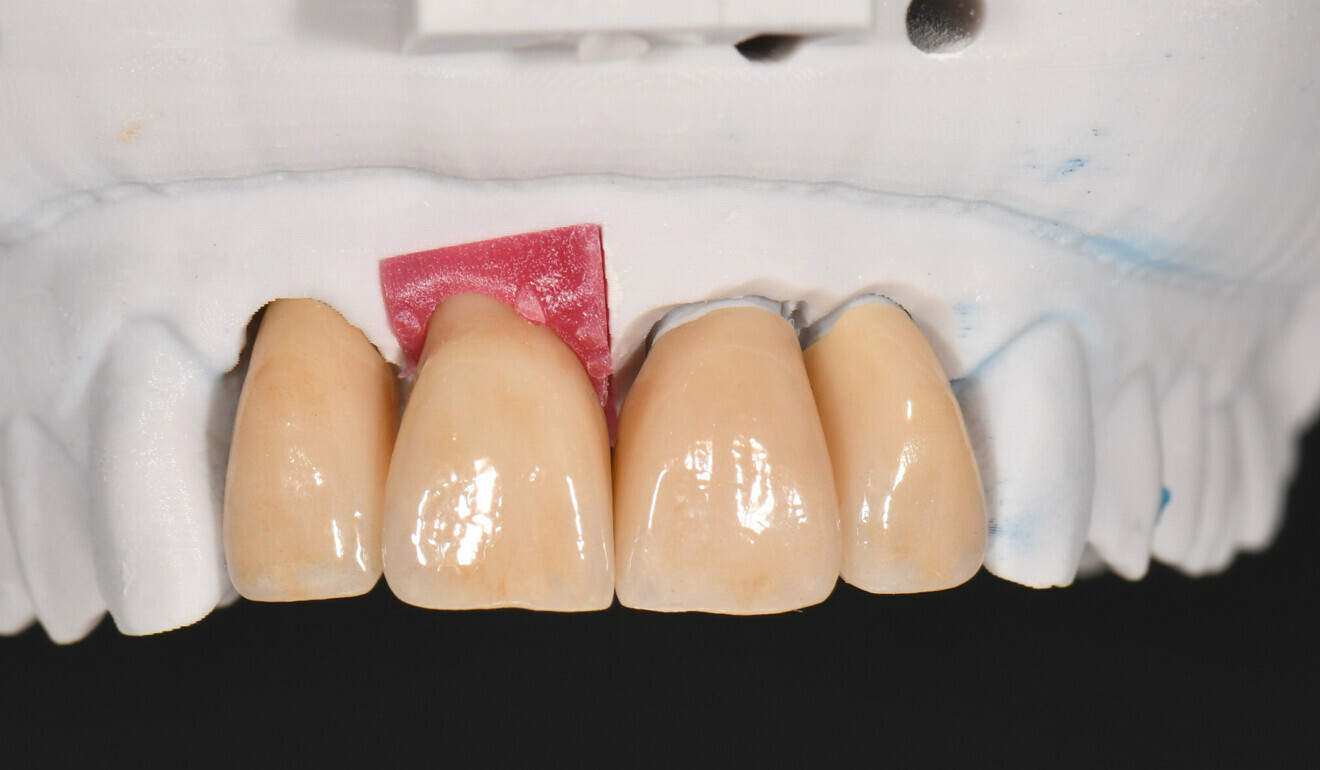

Fig. 5: Printed model with gingival mask.

Fig. 6: Printed model with splinted PMMA crowns.

After the patient’s approval of the aesthetics, phonetics and function of the temporary restoration, the situation was captured with an intra-oral scanner again. This allowed the team to duplicate the shape of the restoration. Based on the data acquired, two pairs of splinted temporary crowns were milled from PMMA (HUGE Multilayer PMMA, HUGE Dental) in Shade A3 in the laboratory (Figs. 5–7). They were placed to allow the patient to further evaluate the appearance and function for several weeks (Figs. 8–10). The patient was happy with the phonetics, function and appearance of the crowns, noting only that they were slightly too bright in comparison with the adjacent teeth, and she approved the shape for the production of the permanent restorations.